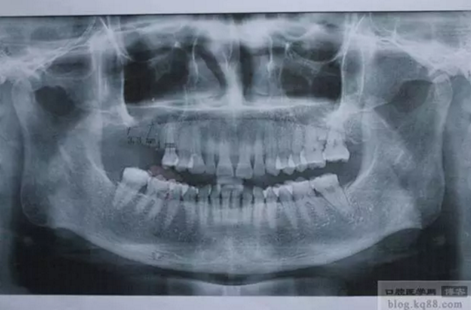

患者:女,49歲,右上6、7缺失,X光顯示右上7骨高度3mm左右,計劃行上頜竇內(nèi)提升同期植入植體。